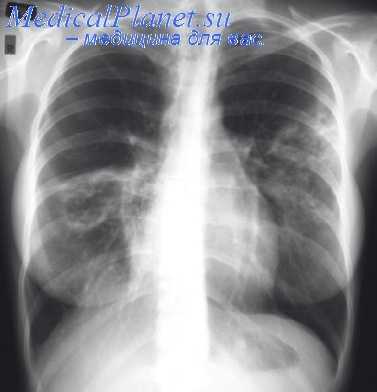

Расширенное разрушение плевральных спаек

При современной комплексной терапии туберкулеза легких хирургическое лечение занимает одно из первых мест. Операция пережигания спаек, являясь самой распространенной, позволяет переводить целый ряд неэффективных пневмотораксов в эффективные. Непережигаемых сращений, по данным разных авторов, в среднем встречается до 70%, куда входят торакоскопии до 25% и частичные торакокаустики—до 45%. Пережиганию спаек методом Якобеуса подлежат лишь отдельные, растянутые до известной степени спайки, а не короткие, более массивные сращения.

В результате показатели эффективности этой операции (соотношение полных пережиганий спаек и частичных каустик и торакоскопии), несмотря на тонкую и высокую технику многих хирургов, остаются почти неизменными до последнего времени. Большинство авторов считает плевральные сращения короче 2 см непережигаемыми. Противопоказанными к пережиганию по вполне понятным причинам являются также короткие спайки, идущие к крупным сосудам (подключичная артерия, дуга аорты, верхняя полая вена и т. д.).

Абсолютно противопоказаны к пережиганию методом Якобеуса все плоскостные сращения, а также многие сращения с глубоким включением легочной ткани, доходящей до грудной стенки. Вопрос о возможности применения более расширенного разрушения спаек стал осуществим лишь с введением метода гидравлической препаровки и анестезии плевральных сращений, разработанного Л. К. Богушем в 1943 г. Этот хорошо известный метод Л. К. Богуша явился одним из способов эффективной борьбы с теми формами и видами плевральных сращений, которые недоступны методу Якобеуса.